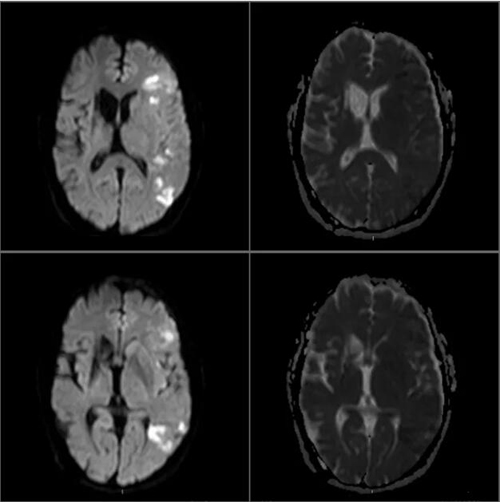

入院后完善相关检查,DWI显示多发脑梗塞;右心声学造影检查回报:右心声学造影阳性(大量RLSIII级),不排除卵圆孔未闭。

我院DWI影像